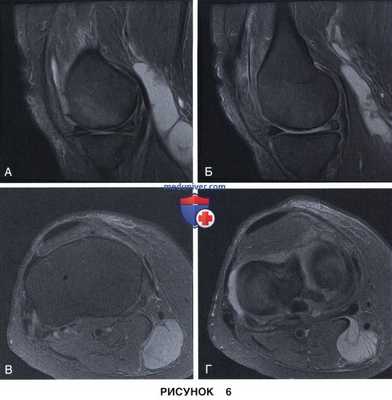

• Неполные разрывы в области верхней или нижней поверхности мениска (рис. 6 и 7)